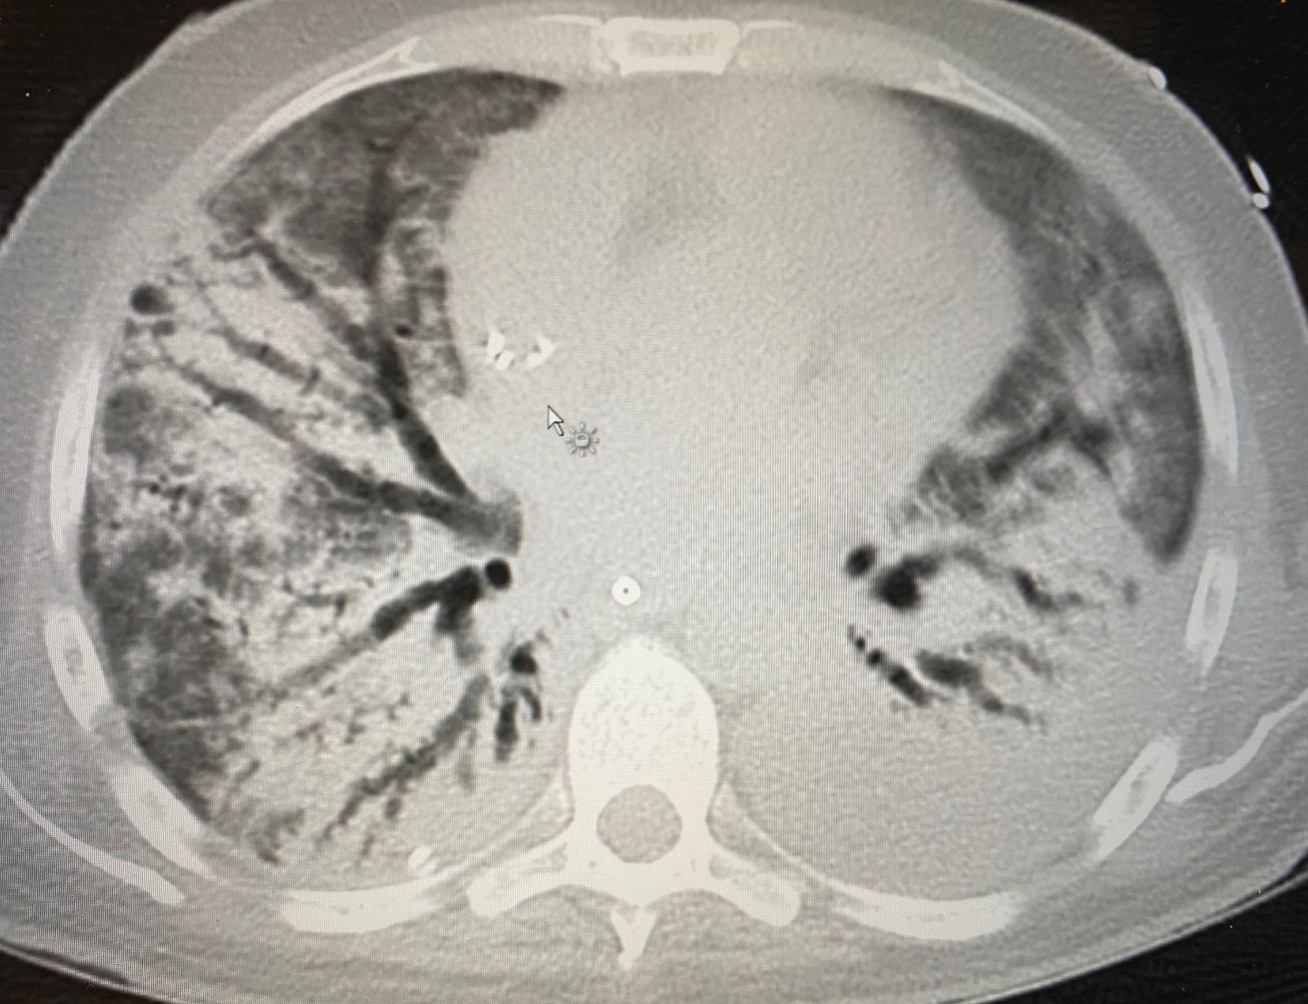

CT scan showing fibrosis developing in ARDS

Professor Ian Adcock, from the National Heart and Lung Institute, aims to investigate the key driving signatures of fibrosis and necrosis in the lungs in COVID-19 patients and relate these to drug-response signatures. The study uses lung samples obtained from the ongoing DeVENT trial. This will identify whether it is possible to repurpose current drugs to treat specific groups of patients with severe COVID-19 patients in ICU or define pathways that are likely to respond to other currently available therapies.